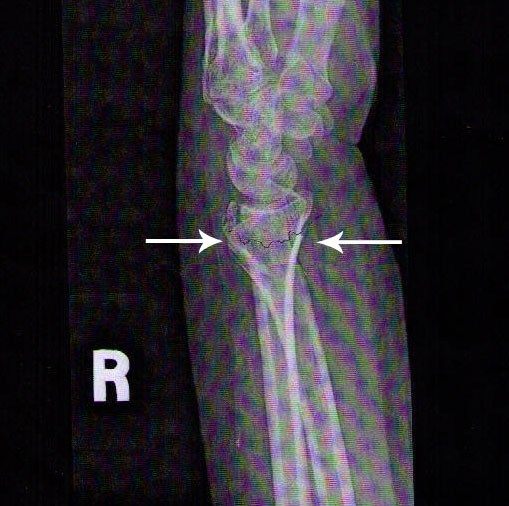

The images below show a wrist break and then after the use of photon light therapy and bone density repairing supplements. This occurred in less than one month.

Initial Break X-Ray